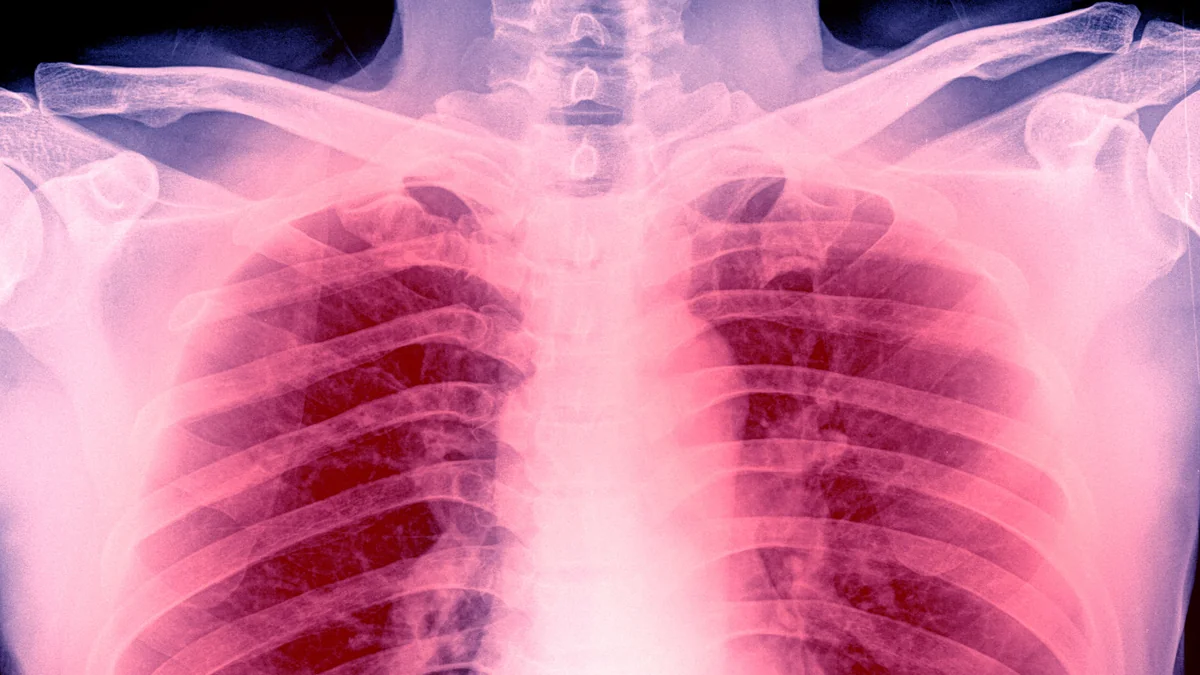

Val Kilmer od 2014 roku zmagał się rakiem gardła, a niedawno zmarł w wieku 65 lat. Jak poinformowała córka artysty, przyczyną śmierci było zapalenie płuc. To globalny problem zdrowotny, dotykający rokrocznie około 450 milionów osób. Wiele z nich nie przeżyje. Rocznie w Polsce z powodu stanu zapalnego umiera ok. 18-25 tys. ludzi. Ekspert ds. chorób płuc twierdzi, że ciężkość tej choroby jest poważnie niedoszacowana. Pewna grupa ludzi jest szczególnie zagrożona i nie ma o tym pojęcia.

Papież Franciszek w ostatnich miesiącach przechodził ciężkie zapalenie płuc. Ryzyko, że 88-latek nie przeżyje, było wysokie. Niedawno w mediach pojawiła się informacja, że głowa kościoła będzie leczyć schorowane płuca w uzdrowisku nad Bałtykiem, w jednej z nadmorskich miejscowości położoną w zachodniej części kraju, blisko granicy. Val Kilmer od 2014 roku zmagał się rakiem gardła, a niedawno zmarł w wieku 65 lat. Jak poinformowała córka artysty, przyczyną śmierci było zapalenie płuc.